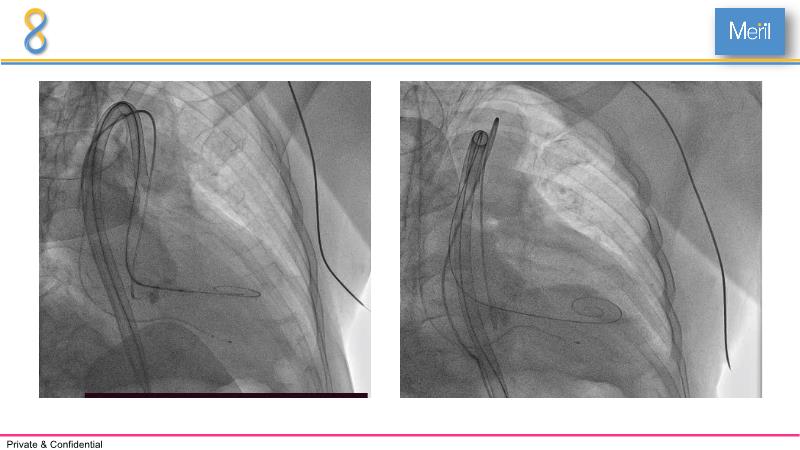

Through the presentation of several compelling cases, including an 88-year-old male with CKD, RBBB, moderate LV dysfunction, and severe aortic stenosis, a Type 1a bicuspid native AS, and an extraordinary TAVI in an 83-year-old with acute heart failure and comorbidities, this session will dive into the Myval Octapro THV. Learn about its key features, procedural impact, and potential clinical benefits. Discover the Octalign technique for predictable and precise commissural and coronary alignment, preserving coronary access. Gain insights into precise sizing, positioning, and deployment of the Myval THV series in real-world scenarios, and explore the relevance of pivotal Landmark RCTs in clinical practice.

- To know the Octalign technique which enables predictable and precise commissural and coronary alignment thus preserving coronary access

- To understand the technique of precise sizing, positioning and deployment of Myval THV series in real world clinical scenarios